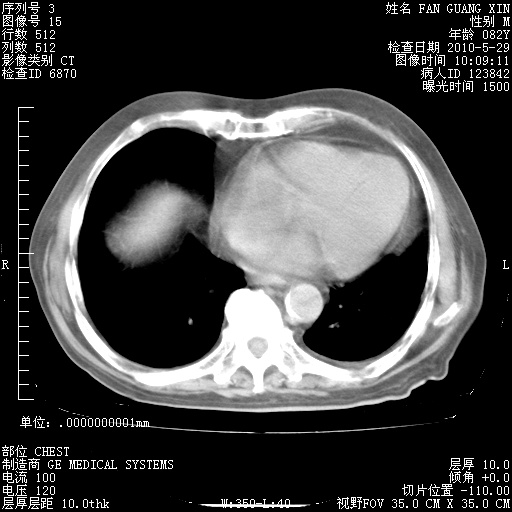

治疗3周后的肺部CT纵隔窗

再治疗10天后的肺部CT

再治疗10天后的肺部CT 纵膈窗

阅读此次胸部CT,肺间质渗出性改变较入院时有吸收。目前从体温、白细胞、中性分叶明显增高,肯定存在细菌感染(发生医院感染哦,若无消化道及泌尿系统等感染的依据,肺部感染可能大)。若你院头孢哌酮舒巴坦钠耐药率较高,同意你的方案,若48小时体温仍高,可考虑使用碳青霉稀类抗菌药物,同时可予超声雾化、注意滴数时加大液体量。白蛋白33.30g/L较低哦,需加强营养等支持治疗。